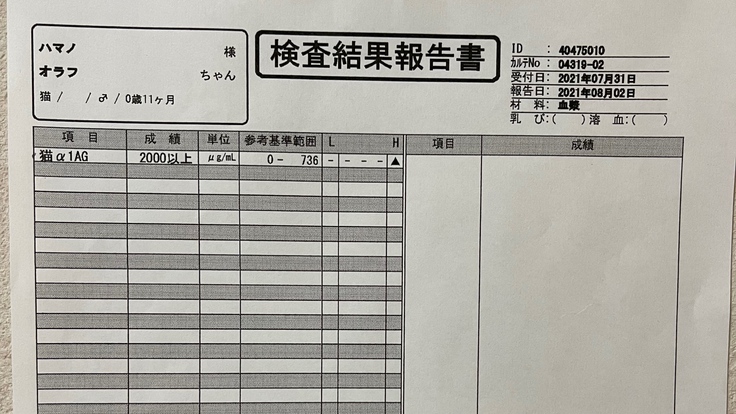

8月2日

オラフのFIP陽性の検査結果が出ました。

炎症度合いの数値も2000以上と正常値ではありませんでした。